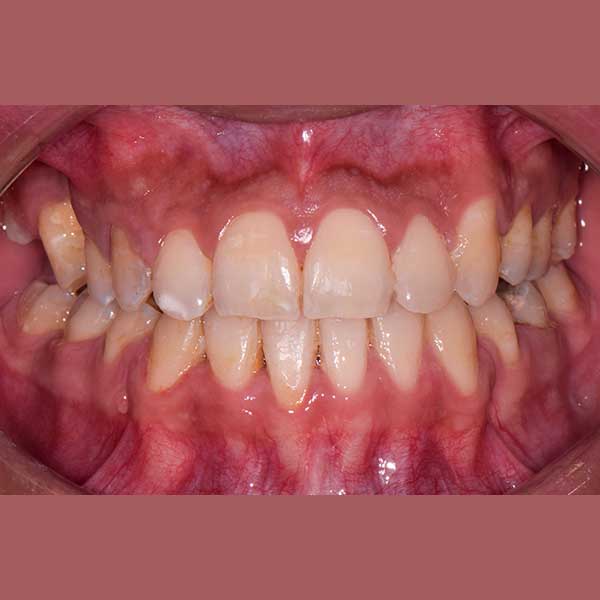

AFTER

ولحسن الحظ في حالتها كان بالإمكان اجراء المعالجة من دون قلع أسنان، وقد اخترت استخدام التقويم ذاتي الربط (تقويم الدايمون) لأنه يساعد في تحريك الأسنان وتوسيع الفكين. وبالفعل، في نهاية العلاج نجحنا في رصف الأسنان بشكل ممتاز، وبات بإمكان مراجعتنا الابتسام بثقة وسعادة مجدداً.